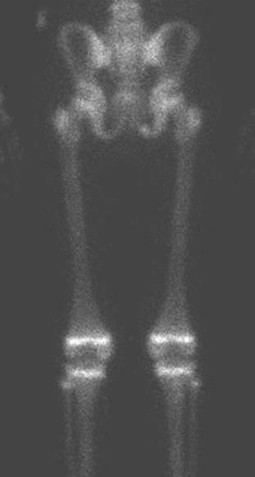

Wat is een botscan?

Een botscan, ook wel skeletscintigrafie genoemd, is een scan van het skelet die wordt gemaakt nadat er een licht radioactieve stof is ingespoten via een infuus. Na het inspuiten van de radioactieve stof moet je een tijdje wachten zodat deze kan worden opgenomen in de botten en gewrichten. Op plekken waar meer activiteit is, verzamelt zich meer radioactieve stof. Met behulp van een gammacamera kan dit in beeld worden gebracht.

Botscan van het bekken, bovenbenen en knieën van een kind van 10 jaar. Op plekken waar het skelet hard groeit, zoals de groeischijven rond de knieën, is veel activiteit zichtbaar. Er zijn geen afwijkingen.

Tijdens het maken van de scan lig je op je rug. De gammacamera wordt vlak boven je gepositioneerd om de radioactiviteit goed te kunnen opvangen.